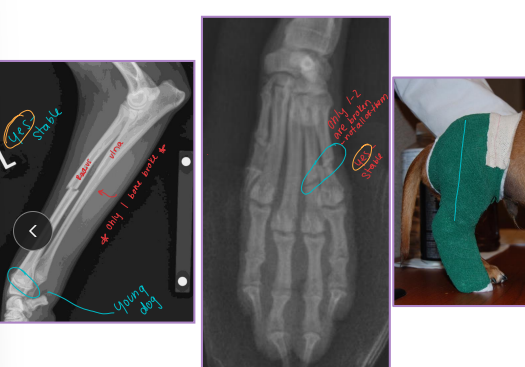

Carpal, Metacarpal, Digital, Metatarsal Fractures

Metacarpal and Metatarsal: medical tx most common

Tx: closed reduction + caudal splint (Rx #1), IM pins/plates + caudal splint (Sx)

Sx indicated if open, grossly displaced, intra-articular, or all 4 fractured

Digital: caudal splint bandage for 6w

Casts

Why: definitive fracture stabilization

indirect bone healing

Fractures are closed, stable (not axial), distal to elbow/stifle, heal quickly!!

How:

Limb immobilized

Closed reduction of fracture

Tape stirrups → stockinette! → casting tape

2-4 layers, 50% overlap

Check:

Rads with >50% reduction needed min

Common complication: rub sores, monitor pressure points!!, weekly checks

Removal: bivalve or saw/spreader

Bivalve: cast can be reused, cut once they are formed for easy cast changes!!